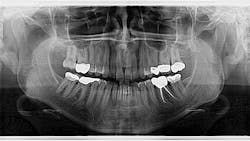

A healthy 45-year-old female presents for her recare exam and an update on her panoramic radiograph. She reports no concerns or complaints.

An assessment of her pan reveals two radiopaque lesions apical to the root tips of nos. 8 and 9, measuring approximately 8 x 4 mm (figure 1). There was no tenderness on palpation in the generalized area. These lesions were noted on previous radiographs, and no changes were present.

Using the Clark tube-shift technique, the positions of both lesions were determined to be separate from the apices of the central incisors. The definitive diagnosis was determined to be impacted supernumerary teeth, or more specifically to this area, mesiodens.